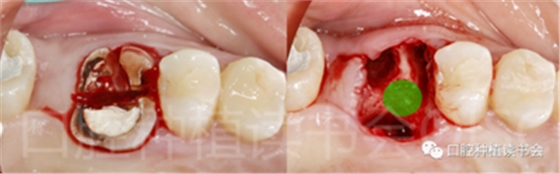

(5)可以有效的關(guān)閉拔牙創(chuàng)(圖2、圖3)。

圖2 初期穩(wěn)定性良好的位點(diǎn),采用愈合基臺(tái)+縫合固定的方法關(guān)閉拔牙創(chuàng),術(shù)后1周獲得良好的軟組織愈合。

圖3 初期穩(wěn)定性不足的位點(diǎn),采用膠原蛋白覆蓋(倍菱)+縫合固定的方法關(guān)閉拔牙創(chuàng),術(shù)后10天獲得良好的軟組織愈合。

5.3.4 旋入覆蓋螺絲,在種植體與四周骨壁的間隙內(nèi)植入 Bio-Oss Collagen,植骨材料用生理鹽水濕潤(rùn)后,用15#刀片分割為小塊分別植入,并用充填器壓實(shí)(圖17)。

圖17 后牙即刻種植植骨推薦使用骨膠原材料,有利于軟組織愈合。

5.3.5 考慮到初始植入扭矩未達(dá)到30N.cm,采用外覆”倍菱“膠原蛋白+縫線固定的方式關(guān)閉創(chuàng)口的方案(圖18)。

圖18 創(chuàng)口使用”倍菱“膠原蛋白保護(hù),促進(jìn)愈合。